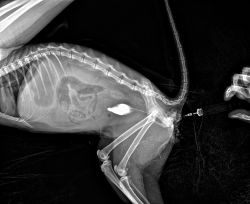

无标题 无名氏 2025-02-22(六)22:42:42 ID:7s7DaLn [举报] No.65353087 管理

肥哥

收起 查看大图 向左旋转 向右旋转

>>No.65353087

光是这张片子看着膀胱没有什么太大异常,( ゚∀。)7但是肛门排尿我还是觉得不太可能